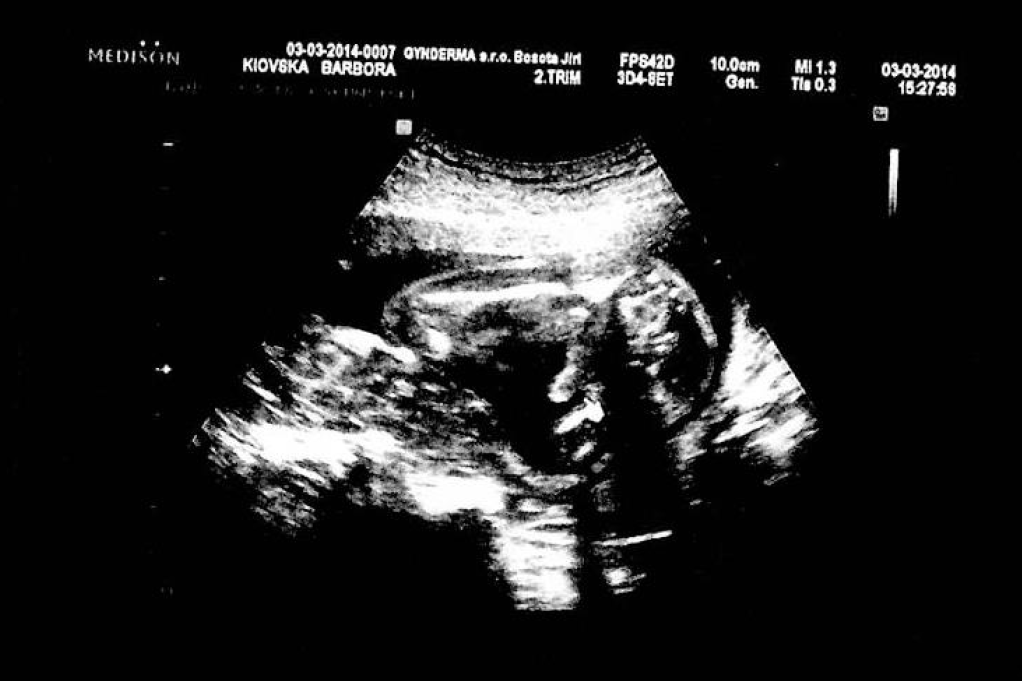

no tam kde je ta šipka tak to je prý penis? a to na těch stranách jsou stehna

[473297]já to tam prostě nevidím, na našem je krásné "kávové zrno", takže u nás je to na 100 % holčička

[473335] Mělas asi lepšího doktora....a lepší ultrazvuk.....